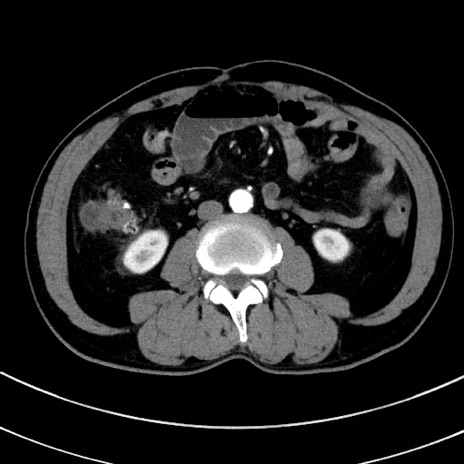

症例8(横断像)

【症例】 60歳代男性

【主訴】 黒色吐物

【現病歴】 4日前から嘔気自覚、2日前の朝食後にも嘔気あり、自分で手で嘔吐反射起こし嘔吐したところ血が混ざっていたため受診。

【既往歴】 5年前汎発性腹膜炎を伴う急性虫垂炎で手術、高血圧、前立腺肥大症、高脂血症

【身体所見】 腹部正中に手術癩痕あり 腹部平坦・軟圧痛なし膨満感あり

【データ】WBC 8400、CRP 4.54